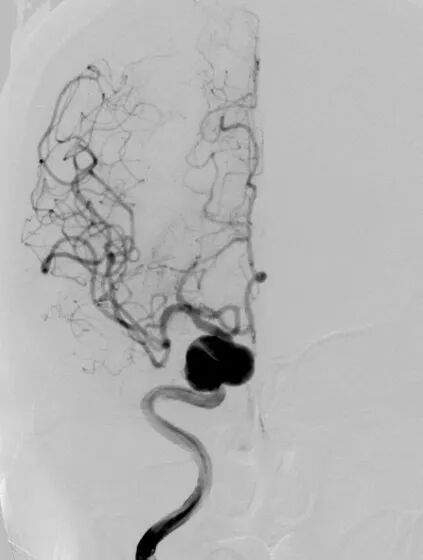

术前影像学检查CTA显示右侧颈内动脉海绵窦段巨大型动脉瘤。

术前3D显示右侧颈内动脉海绵窦段巨大型动脉瘤

DSA正位造影

动脉长鞘怎么置入深谋远路 | 千人皆翘首,万唤今始来——国内首款7F长鞘在血流导向密网支架联合弹簧圈栓塞治疗动脉瘤的首次应用_https://www.jmylbn.com_新闻资讯_第5张

DSA侧位造影